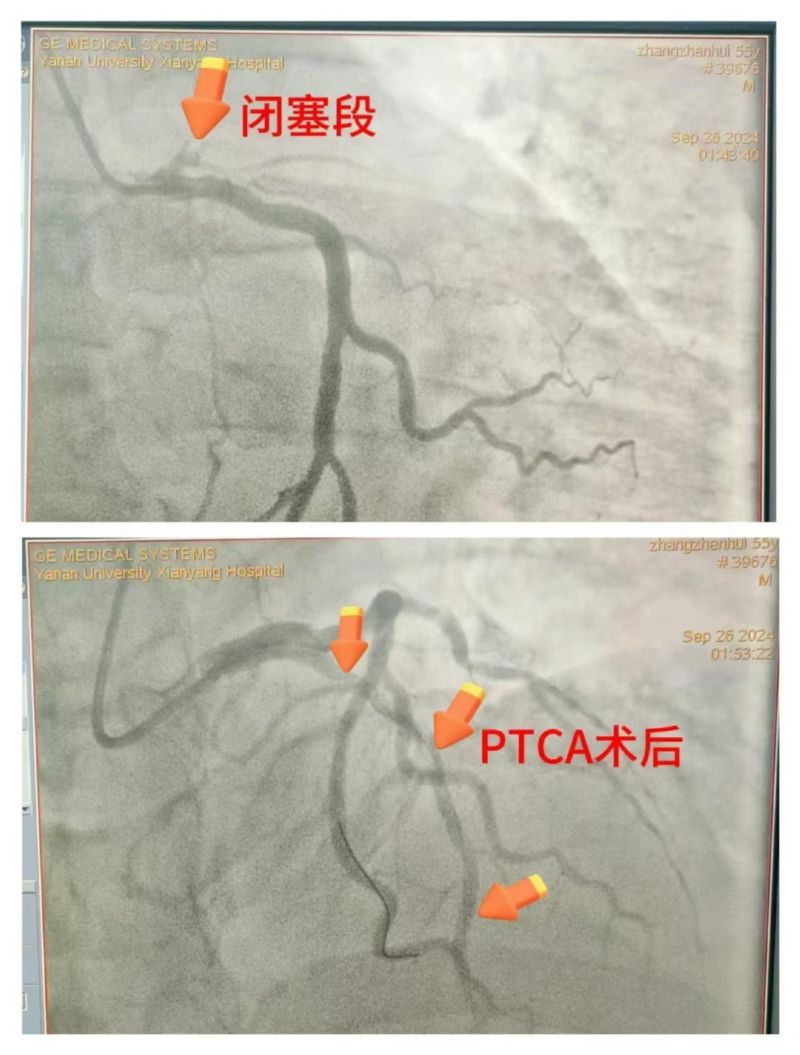

患者仍反復(fù)室顫,考慮與急性心肌梗死、急性胰腺炎導(dǎo)致的電風(fēng)暴相關(guān),唯一的希望是開通罪犯血管,但手術(shù)風(fēng)險極高。李新國科主任與患者家屬充分溝通病情,家屬理解并配合一切治療方案。立即開通胸痛綠色通道,啟動導(dǎo)管室行急診冠脈造影,術(shù)中證實為左前降支近段100%閉塞,緊急行PTCA開通罪犯血管,患者心律逐漸穩(wěn)定,血壓回升,意識好轉(zhuǎn),刺激有反應(yīng),返回CCU繼續(xù)治療。